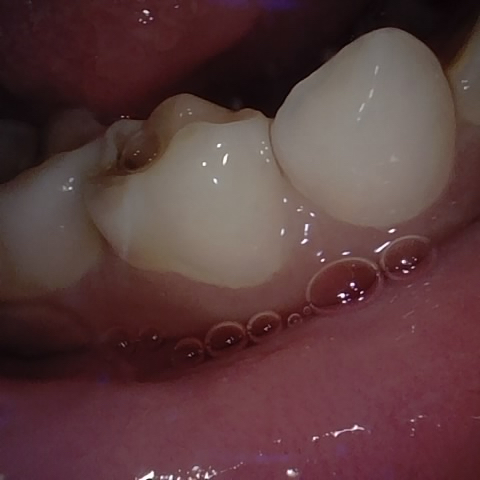

Annotated as "Good"